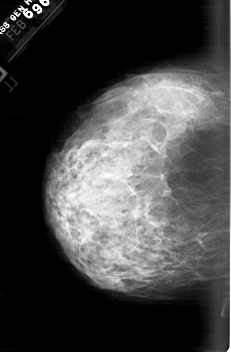

A_1564_1.RIGHT_MLO

RIGHT_MLO LINES 6271 PIXELS_PER_LINE 4501 BITS_PER_PIXEL 12 RESOLUTION 43.5 OVERLAY